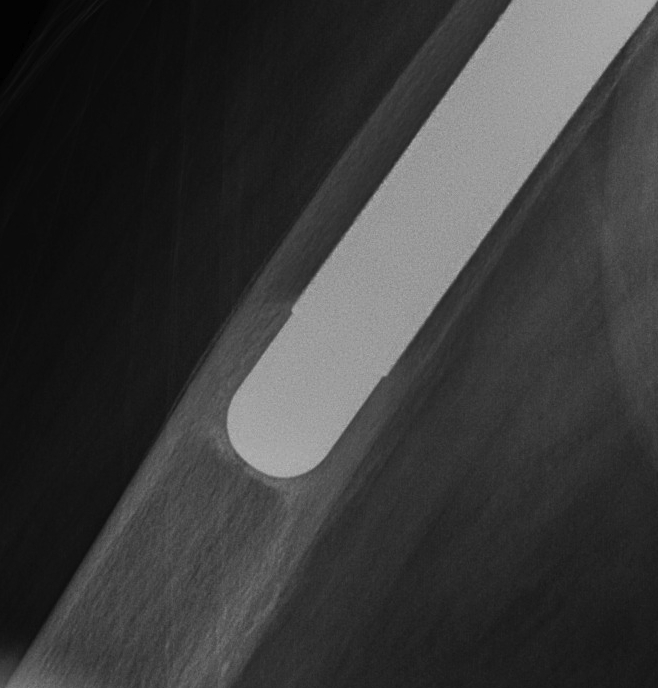

Uncemented femur

Engh classification

Types based on presence of radiolucent lines (RLL)

III Unstable fibrous ingrowth

A.  Component migration

B.  Progressive increase RLL

- divergent RLL

C.  Pedestal formation (bony hypertrophy at tip)

THR Uncemented Subsidence